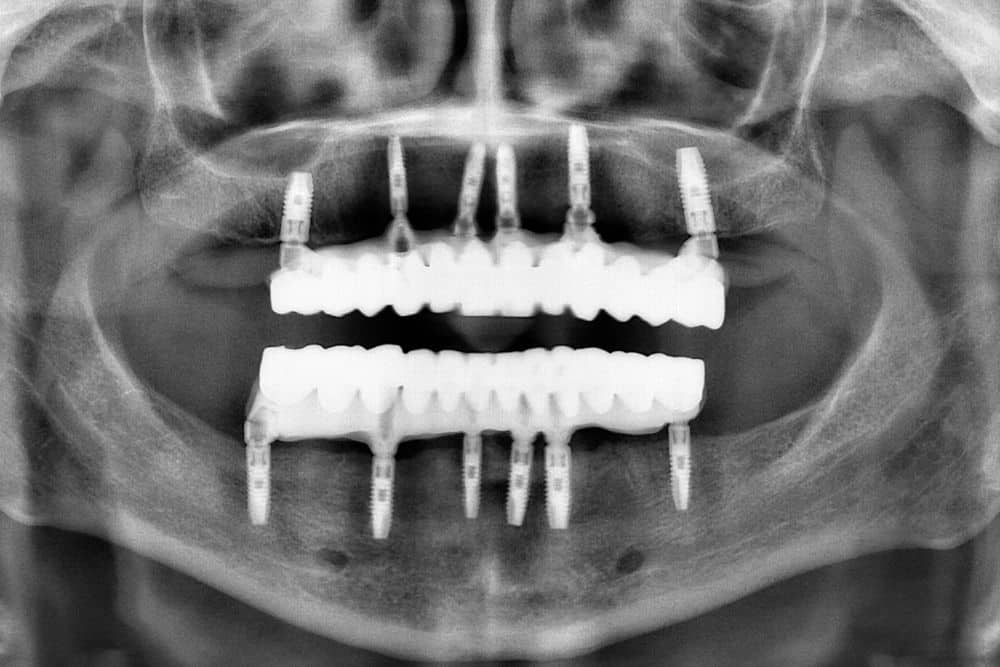

Kao i u slučaju mnogih drugih zahvata iz domena oralne hirurgije i implantologije, pre početka sinus-lifta neophodna je izrada RTG i CT-snimka. Na osnovu ovih snimaka, oralni hirurg određuje visinu i širinu alveolarne kosti i procjenjuje stanje maksilarnog sinusa.

Zubni implanti posljednjih decenija imaju preimućstvo u odnosu na druge vidove dentalnih nadoknada. Izrađeni su obično od titanijuma (ponekad od cirkonijuma) i kao takvi najbolji su zamjenici izgubljenih zuba. Njima se postiže dobra stabilnost zuba, prirodan izgled vilica i normalno žvakanje i govor.